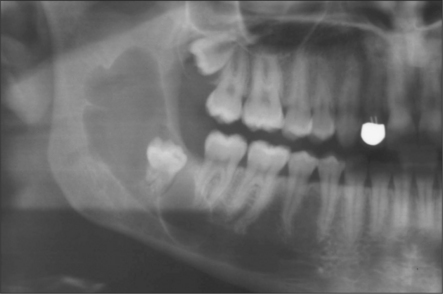

MAXILLARY THIRD MOLARS

Indications for removal

Extraction is indicated if the tooth is erupted and causing trauma to the cheek or operculum overlying the lower wisdom tooth. Unerupted third molars are often asymptomatic and unless there is associated pathology (Fig. 5.20) they should be left, regardless of whether the lower third molars are to be removed under general anaesthesia.

image

Fig. 5.20 Bad taste associated with unerupted upper third molar. Little radiographic (a) or clinical evidence for the large dentigerous cyst (b) removed with the wisdom tooth.